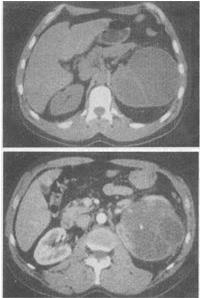

5、 女,48岁,左腰部胀痛不适2个月余,根据所示图像,最可能的诊断是()。

- A、左侧囊性肾癌

- B、左侧肾囊肿

- C、左侧多囊肾

- D、左侧肾脓肿

- E、左侧肾积水

【正确答案-参考解析】:参加考试可见 点击进入查看